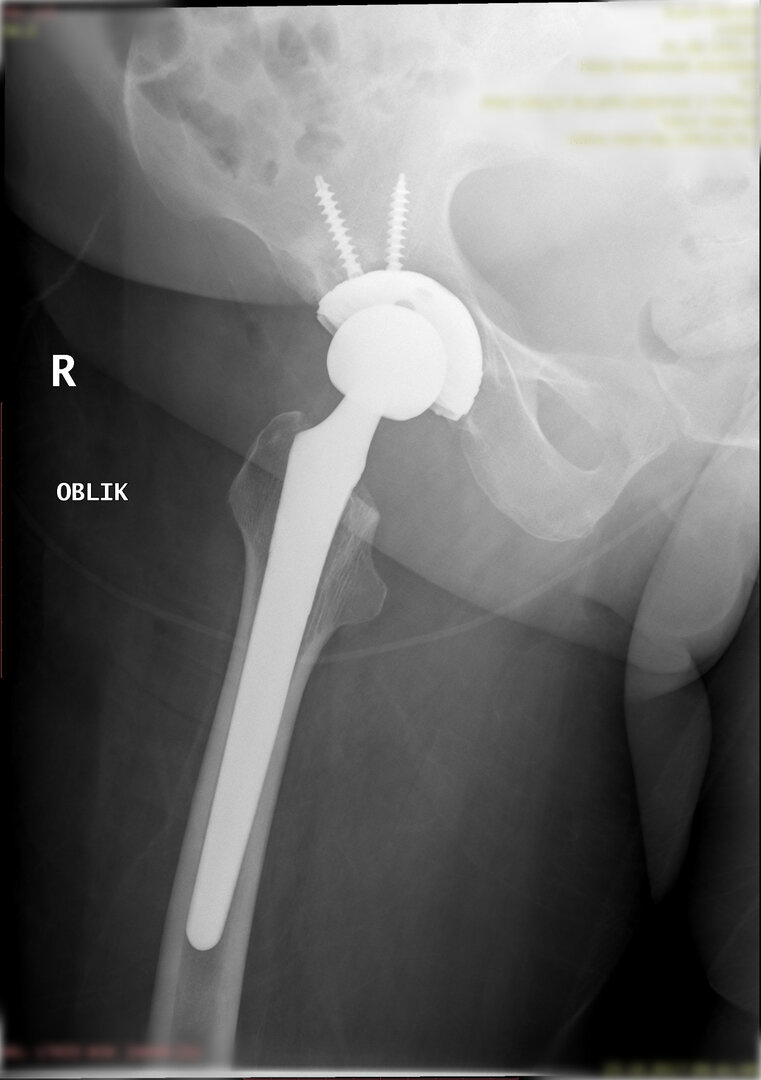

Peki kalça protezi ameliyatın da neler yapıyoruz? Diz protezi ameliyatındaki benzer aşamaları uyguluyoruz. Kalça eklemi dize göre yapısal olarak ve çalışma sistemi olarak farklıdır. Kalça eklemi bir yuva ve onun içinde hareket eden femur başı dediğimiz bir toptan oluşur. Kalça eklemi kireçlenmesinde bu baş ve yuva yüzeyindeki kıkırdakların aşınması sonucu başın yuvarlaklığı kaybolur, sonuçta ağrı ve hareket kısıtlılığı ortaya çıkar. Bu yüzeyleri değiştirirken öncelikle bu başı kesip atıyoruz. Daha sonra yuvayı yine kılavuzlarla oyup uygun büyüklükteki protezi sıkıştırdıktan sonra en az 2 vida ile kemiğe adapte ediyoruz. Daha sonra alt uyluk kemiğini yine kılavuzlar yardımı ile oyduktan sonra kemiğe adapte ediyoruz ve sistemi birleştiriyoruz.

Büyütmek için üzerine tıklayınız.